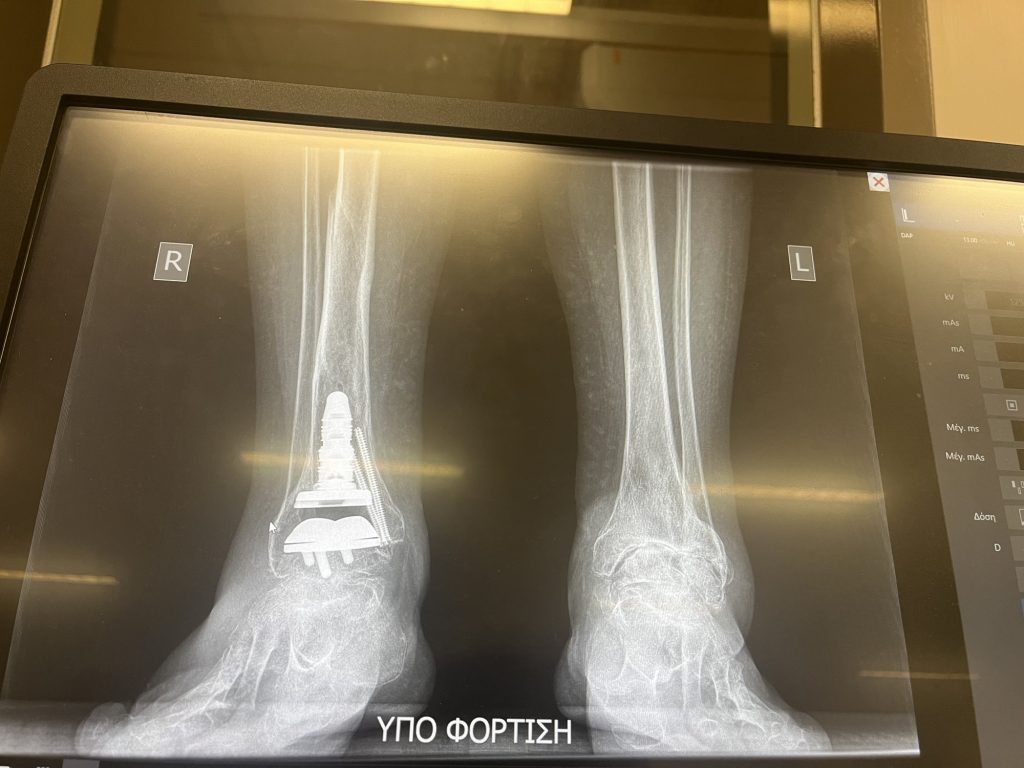

To put things in perspective, allow me to describe my situation and how I came about to consider an ankle replacement surgery – a non-trivial operation as we all know. In my early twenties I broke both legs skiing, and later in my fifties, I developed post-traumatic osteoarthritis in both ankles. Last year the right ankle, which was most problematic, reached its walking limits. In addition, I developed pulled Achilles tendonitis which made walking extremely painful, difficult, and impossible.

Dr. Demetracopoulos performed the surgery on March 27, 2024 and I choose to stay at the hospital for two nights until my hired caregiver was available. After that, all my post-surgery recovery took place at my home with the help of the caretaker who stayed with me for two months, before I returned to Athens and resumed my physiotherapy there.

Dr. Demetracopoulos and his HSS team were wonderful and the results were amazing. I am so pleased beyond description. Nine months later, I have ZERO arthritic pain on my right ankle. I walk freely, my foot looks 10 times better, and have not taken any pain relievers since the surgery and the post-recovery. Given that the full recovery is 12-months and I am now three-quarters into it, I have full mobility. I can easily walk one mile or thereabout, without pain, something that was unthinkable before.